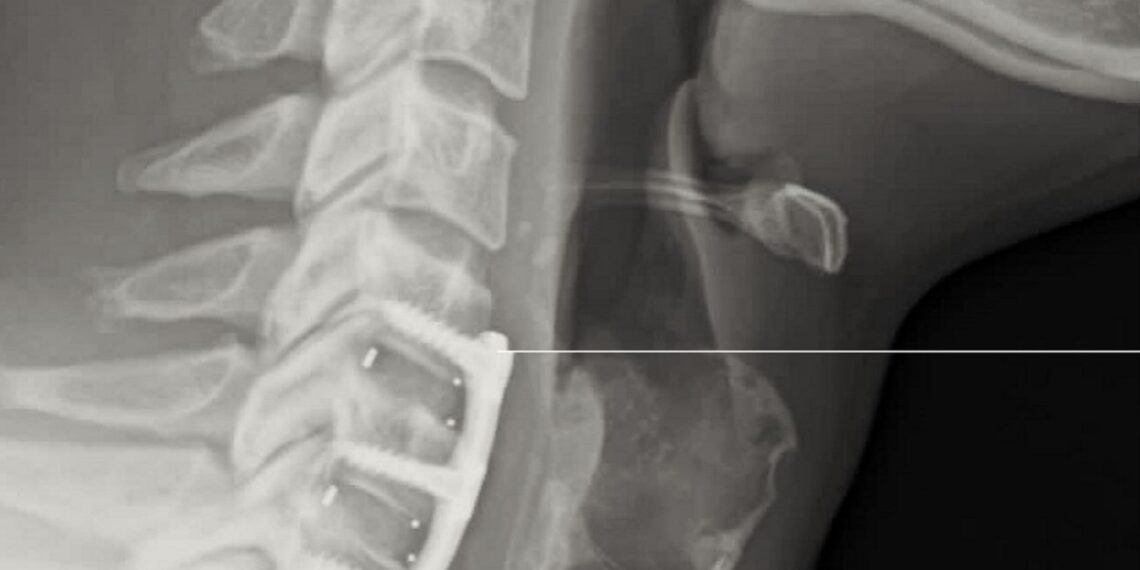

Will Ospreay’s recovery from neck surgery appears to be progressing well, according to a new update from the Body Alignment Clinic in the UK.

The clinic posted an update on Saturday noting that Ospreay is “doing great” six weeks after undergoing neck surgery in mid-September. The post included the caption “Jan 2026”, which appears to indicate the possible timeframe for his in-ring return.

“AEW Allstar Will Ospreay six weeks post op and doing great! Still some way to go with but we’re on the right road,” the statement began. “Jan 2026. Don’t Try This At Home!”